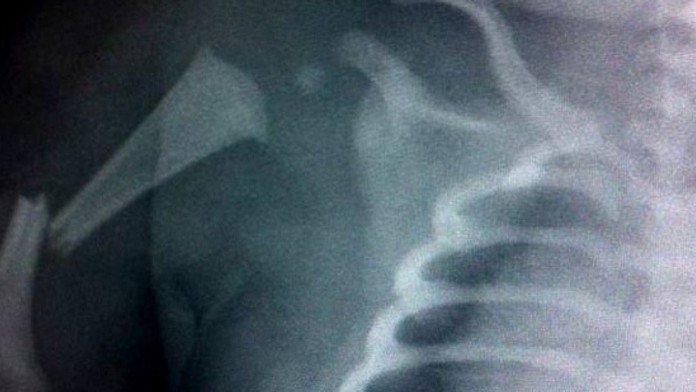

V Británii dievčatku pri pôrode naschvál zlomili ruku

Lekár naschvál zlomil vo Veľkej Británii dievčatku ruku počas pôrodu. Dieťa sa totiž zaseklo a hrozilo, že sa udusí, upozornil portál dailymail.

Malá Poppy vážila viac než päť kilogramov, takže jej príchod na svet bol náročný.

"Lekárom sa nemôžem dostatočne odvďačiť, za to že jej zlomili ruku. Inak by tu už dnes nebola," zhrnula mama dievčatka.